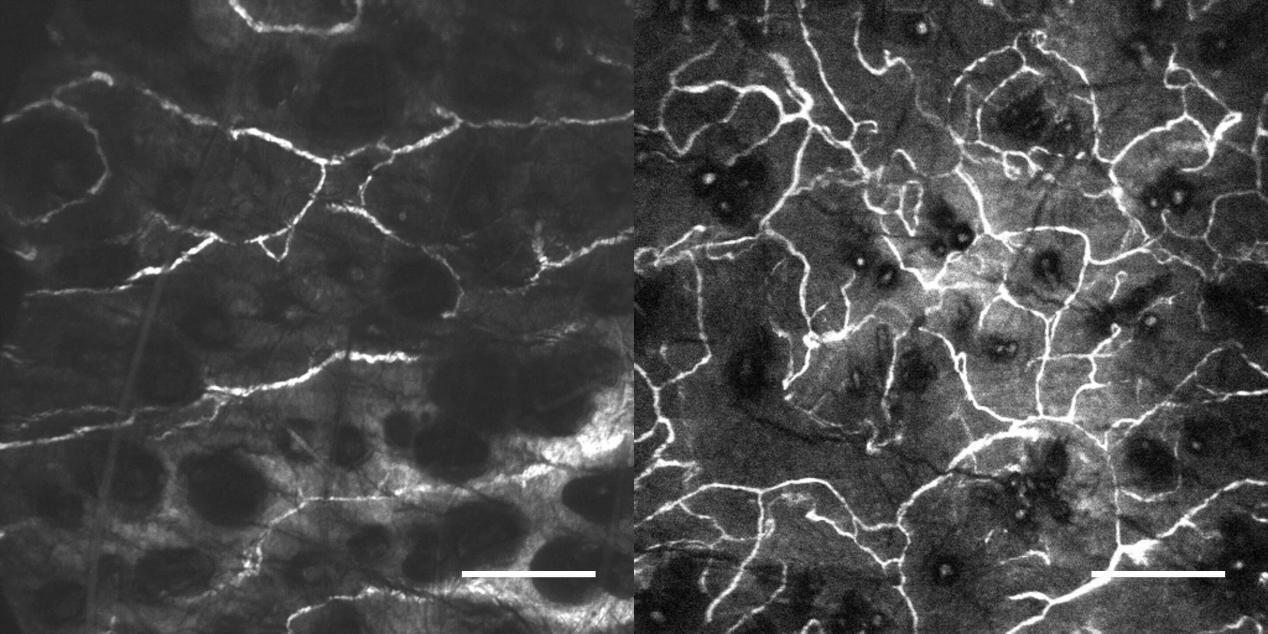

2、宮頸癌OptiScan成像

左:正常鱗狀上皮;右:宮頸上皮肉瘤變。

注:0.05%吖啶黃溶液外用。Scale bar=100μm。